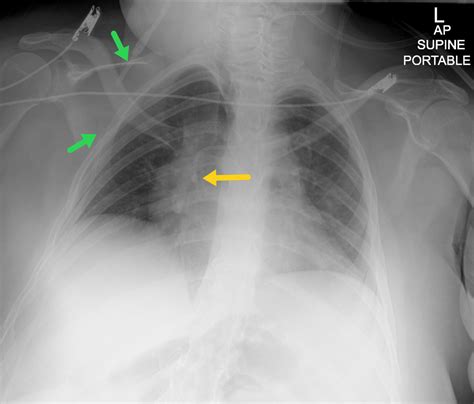

Diagnostic Approaches for Identifying Shunts

Diagnosing a Right To Left Cardiac Shunt requires sophisticated imaging and physiological testing. Physicians often begin with a physical examination, listening for specific heart murmurs that indicate blood flowing through an abnormal orifice. Once a shunt is suspected, the following tests are commonly employed:

• Echocardiography with Bubble Study: A saline solution is injected into the vein; if bubbles appear on the left side of the heart shortly after appearing on the right, a shunt is present.

• Cardiac Catheterization: This is the gold standard, allowing doctors to measure pressure gradients and oxygen saturation levels directly within the heart chambers.

• Cardiac MRI or CT Scan: These imaging modalities provide high-resolution anatomical details of the heart's structure, identifying the exact location of the defect.

• Pulse Oximetry: Used to measure the level of oxygen in the blood, often showing values lower than normal in resting states.